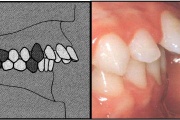

Esimese jäävmolaari ektoopiline lõikumine